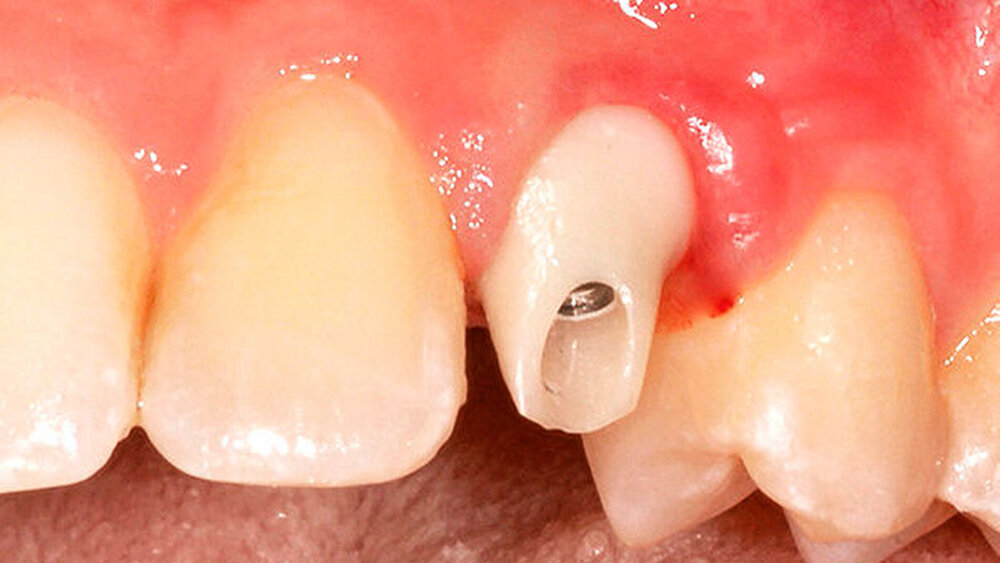

Ja, denn beide haben ihre Pluspunkte. Für unsere Chairsideversorgungen unmittelbar nach der Freilegung wählen wir zum Beispiel ausschließlich konische Innenverbindungen, um sicherzugehen, dass kein Weichgewebe eingeklemmt wird.

Es besteht jedenfalls ein Risiko, das ich nicht eingehen möchte. Mit einem verzögerten CEREC-Protokoll wäre man auch mit Butt-Joints auf der sicheren Seite. Nach dem Einbringen des Gingivaformers sollte vor der definitiven Versorgung eine Woche verstreichen, bis das Gewebe soweit adaptiert ist.

Auf jeden Fall! Neben einer besseren Ästhetik, gerade bei der Verwendung von Zirkon, ist die Lage des Übergangs Abutment-Krone bei zementierten Arbeiten von enormer Wichtigkeit. Werden aufgrund zu tief subgingival liegender Kronenränder Zementreste unzureichend entfernt, stellt dies eine der Hauptursachen für eine frühe Periimplantitis dar.